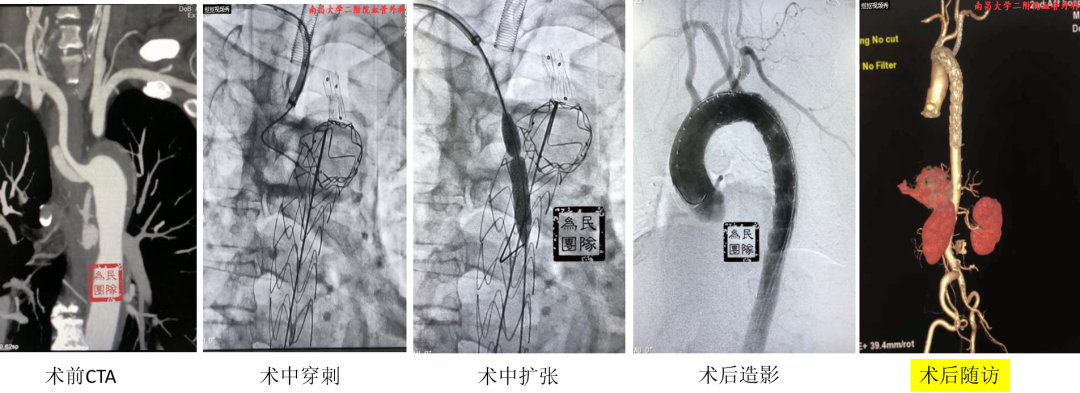

【体外预三开窗】精准规划的选择

体外预开窗技术是根据术前测量结果,在支架上预留对应分支开口,支架释放后开口对准分支开口以保留分支血供。

技术改进:通过3D打印模型辅助术中操作,先对准左颈总动脉,再对准左锁骨下动脉,用球囊扩张固定后再释放支架,为纠错和防止移位争取时间。

复杂病例应用:巨大弓部动脉瘤(5.5cm)且左锁骨下动脉位于瘤腔内:在预开窗基础上加做左锁骨下动脉内嵌分支,配合3D打印模型辅助和束径技术,术后随访效果理想

A型夹层合并迷走左椎动脉:针对头臂干、左颈总和左锁骨下动脉进行预开窗,对非优势且纤细的迷走左椎动脉仅作小洞处理,术中对位良好